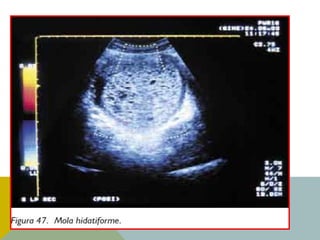

• Ecografía. Es la técnica diagnóstica de

elección. Se aprecia una imagen característica

en copos de nieve que corresponde a las

vesículas hidrópicas. No se ve saco

gestacional ni presencia de feto, pero las

imágenes no son especí.cas, ya que pueden

aparecer imágenes similares en miomas

coincidentes con gestación temprana.

DIAGNÓSTICO

• El diagnóstico de certeza nos lo da la

anatomía patológica tras el legrado.

• Ecografía. Esla técnica diagnóstica de elección. Se aprecia una imagen característica en copos de nieve que corresponde a las vesículas hidrópicas. No se ve saco gestacional ni presencia de feto, pero las imágenes no son especí.cas, ya que pueden aparecer imágenes similares en miomas coincidentes con gestación temprana. DIAGNÓSTICO • El diagnóstico de certeza nos lo da la anatomía patológica tras el legrado.